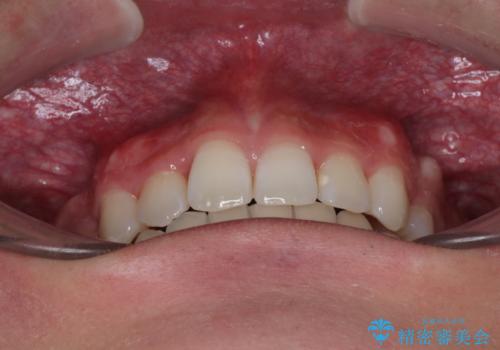

- 今回ご紹介するのは、

「全体的なデコボコ(叢生)」「上下の正中のずれ」 を主訴として来院された20代男性の患者様の症例です。

叢生が強く、歯が並ぶスペースが不足していたため、

上下左右の第一小臼歯を抜歯して、矯正治療のための適切なスペースを確保する計画としました。

上顎左側第一大臼歯に齲蝕が認められたため、矯正治療終了後に 精度の高いセラミックインレー にて修復治療を行いました。